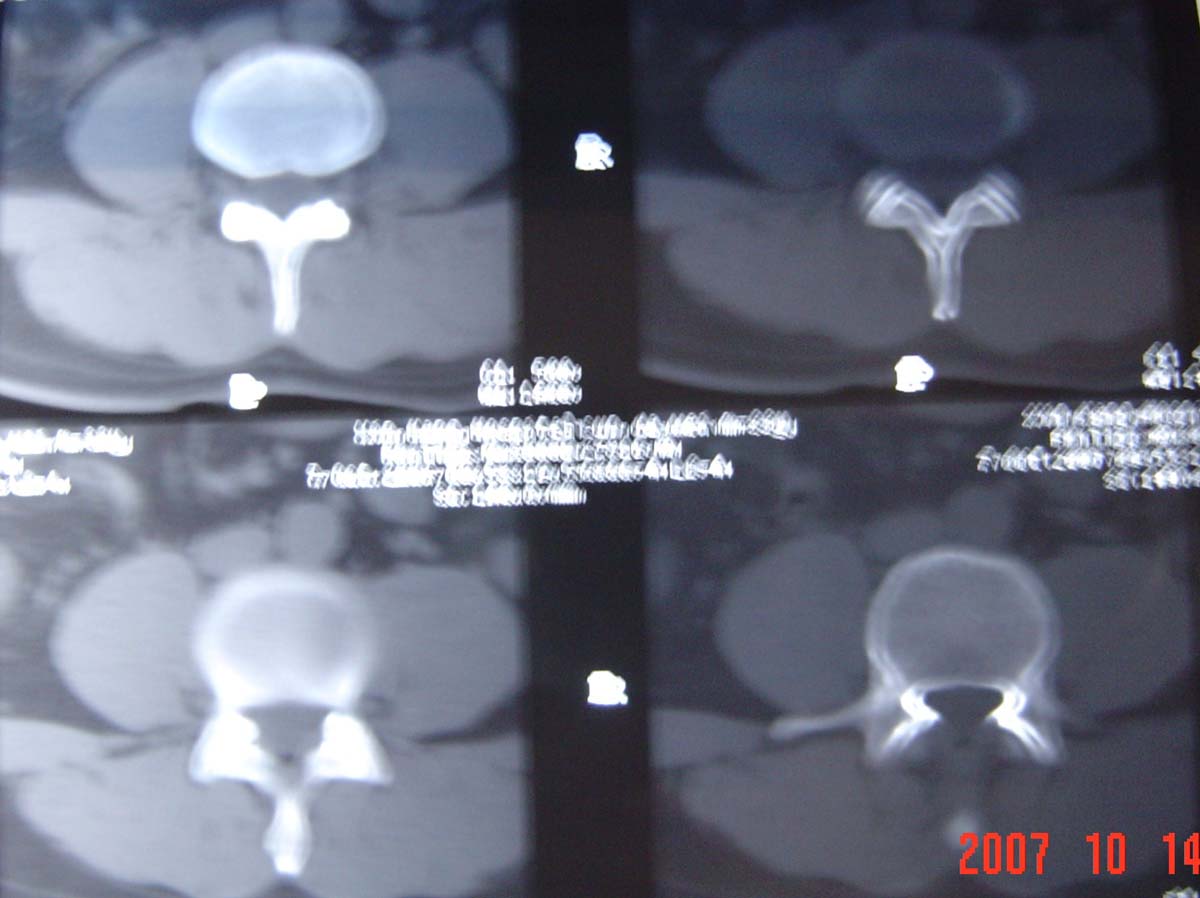

本人的片子,腰腿痛多年,时轻时重。请各位老师发表高见!

1.l4~5间盘膨出伴突出(中央型)

2.l5-s1后纵韧带钙化.